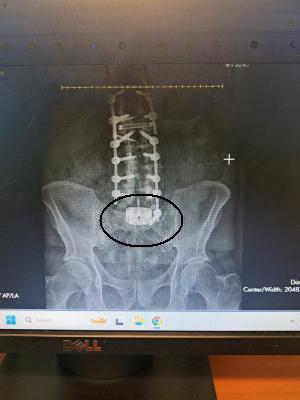

Disc Between L5 & S1 .